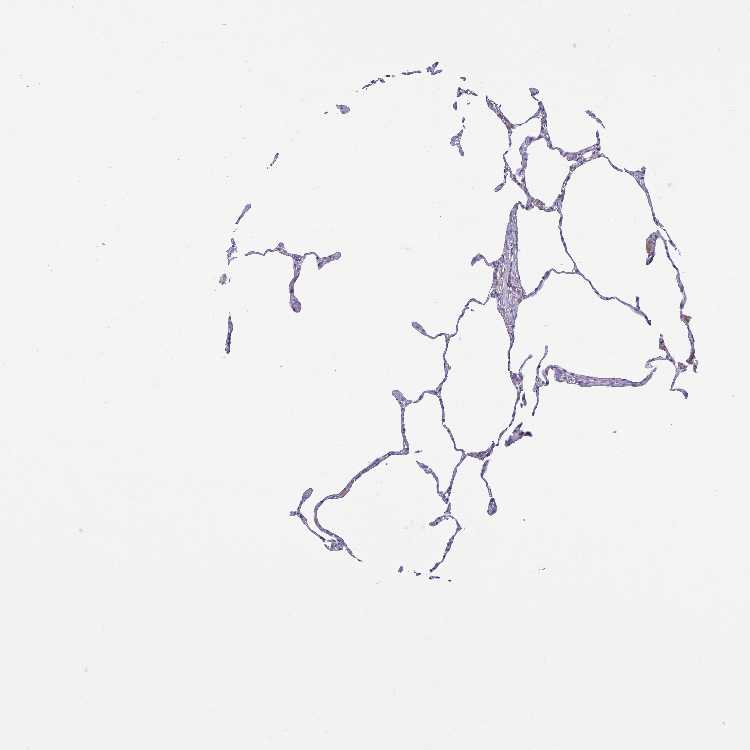

LUNG - Antibody stainingi

Antibody staining in the annotated cell types in the current human tissue is reported as not detected, low, medium, or high, based on conventional immunohistochemistry profiling in selected tissues. This score is based on the combination of the staining intensity and fraction of stained cells.

Each image is clickable and will lead to virtual microscopy that enables deeper exploration of all samples and also displays staining intensity scores, fraction scores and subcellular localization as well as patient and tissue information for each sample.

Antibody HPA057763

Alveolar cells Not detected

Macrophages Low